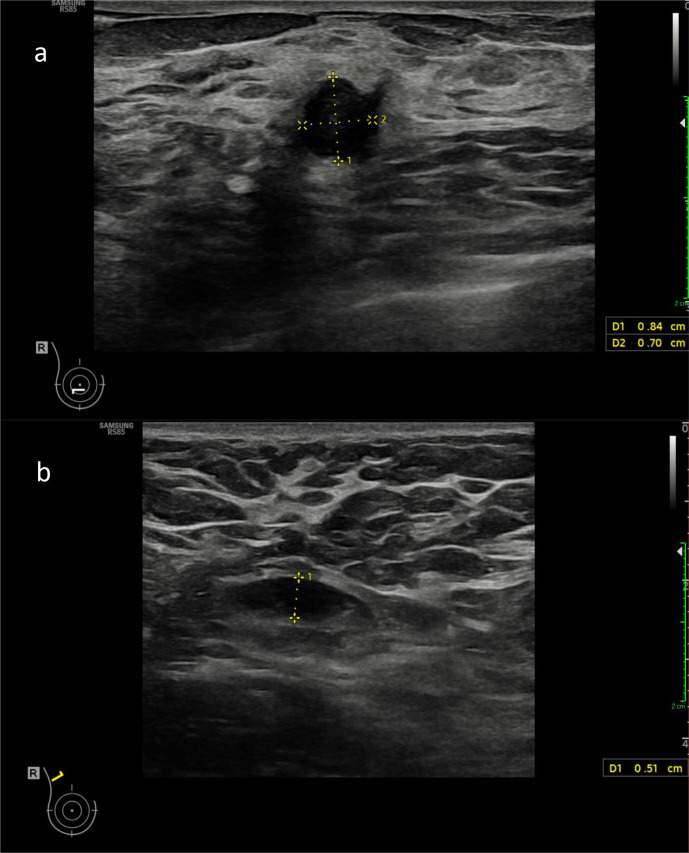

A number of COVID-19 vaccines have been approved worldwide to help tackle the pandemic. As with many vaccines, this causes a reactive axillary lymphadenopathy which can mimic potentially metastatic disease in a breast screening patient. It is therefore important to be aware of this side-effect of the vaccination when evaluating the axilla in a breast screening patient. We present a case of biopsy-proven unilateral reactive axillary lymphadenopathy in a high risk BRCA carrier following administration of the Astra Zeneca vaccine.

Abstract Image